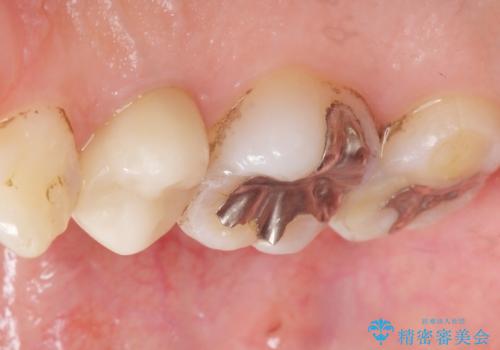

- 低予算で銀歯を白くしたいとご希望し来院された患者様です。

右上小臼歯(右上5)はオールセラミッククラウン(e-max press)、下顎臼歯(下顎両側67)はメタルボンドクラウンによりやりかえることにしました。

再根管治療はご希望されず、行っておりません。